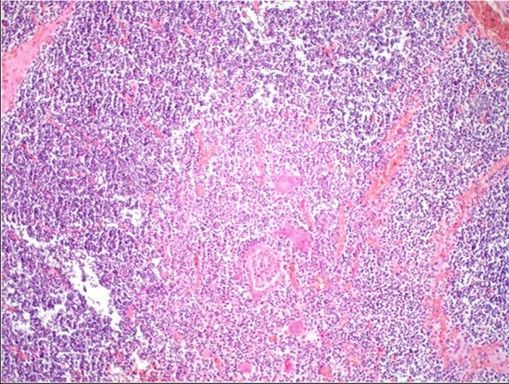

Question 9

Question

Label this image

Image:

2b3c217b-b736-41d9-8396-2e279e9243f6 (image/jpeg)

Answer

Thymus